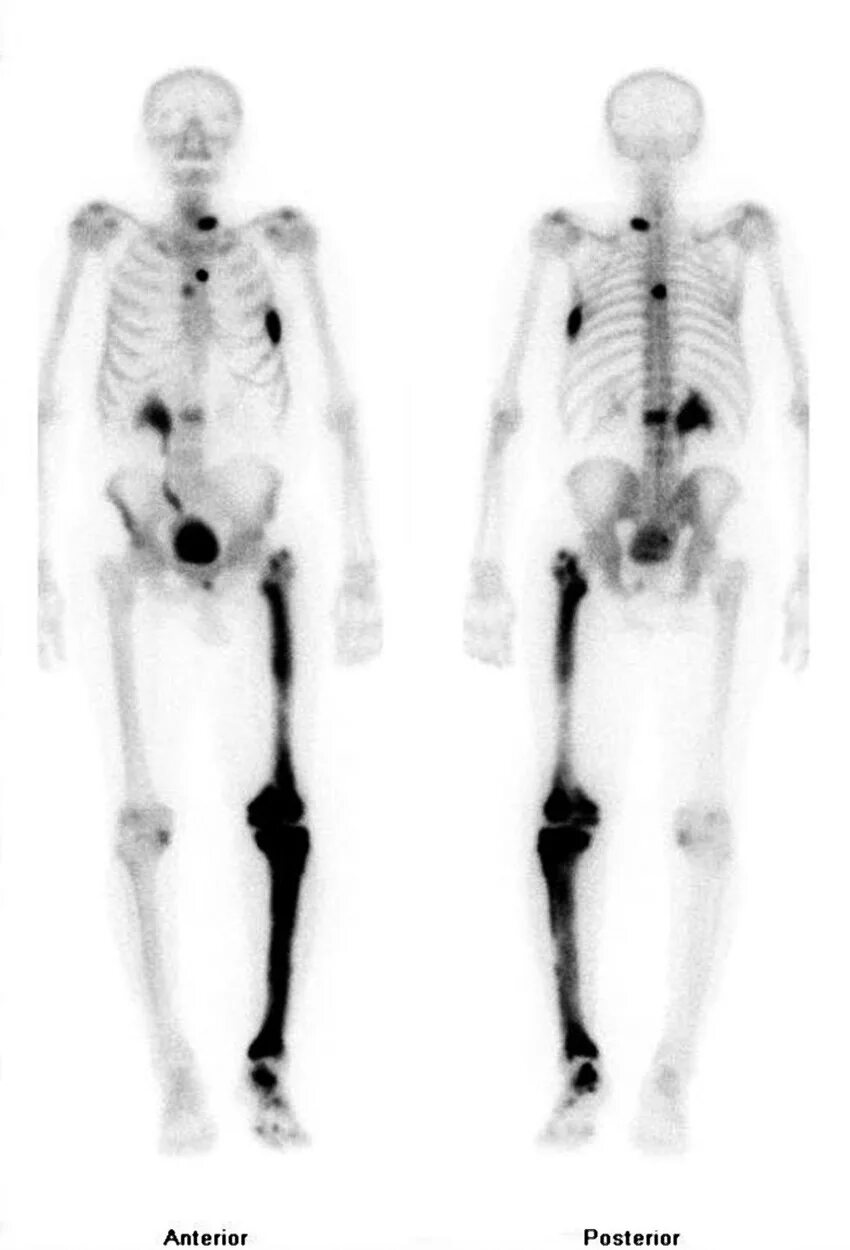

Метастазы костей скелета